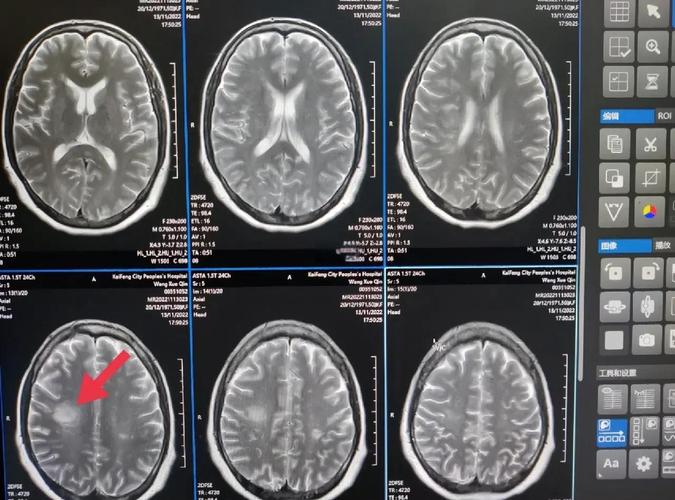

核磁共振如何诊断“脑梗塞”?

脑梗塞,俗称“中风”,是由于脑部血管堵塞导致局部脑组织缺血、缺氧而发生的坏死,MRI是诊断急性期和超急性期脑梗塞最敏感的检查。

- MRI (特别是DWI序列):能在梗塞发生的几分钟到1小时内就发现异常,DWI对细胞毒性水肿(梗塞最早期的表现)极为敏感。

- 急性期脑梗塞:在DWI上呈明显高信号,而在ADC图上呈低信号,这是诊断急性脑梗塞的“金标准”。

对梗塞后几天到几周的亚急性和慢性期病变显示更佳,它能清晰地显示脑沟、脑回的形态,梗塞区域在FLAIR上呈高信号,并且能更好地显示早期的皮层下梗塞。